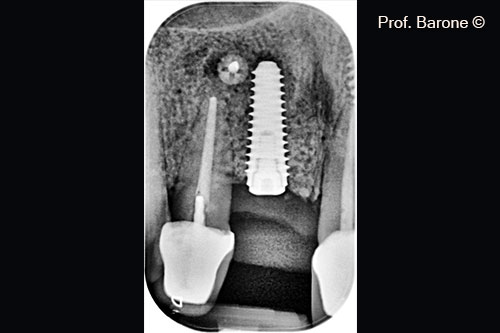

Periapical Radiograph 3 months after implant placement